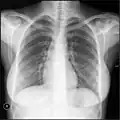

Zdjęcie klatki piersiowej